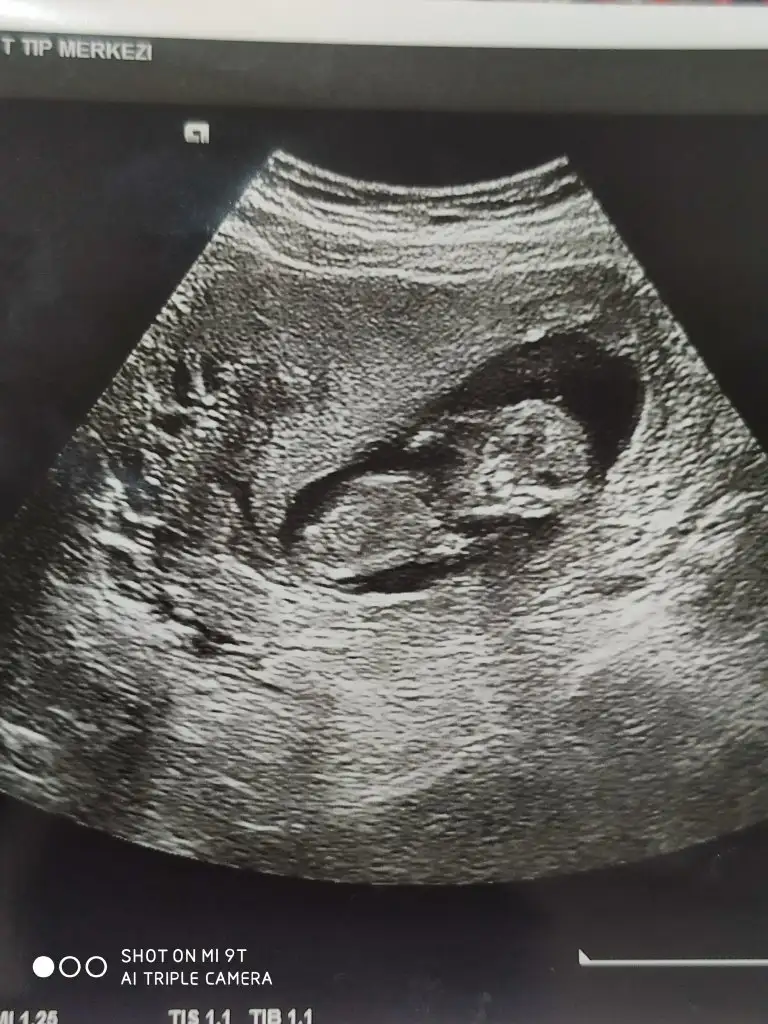

Merhaba buda 13 haftalık acaba şimdi netleşir miKarından ise erkek vajinalsa kiz tabiki en iyi 11 12 13 haftalar

Erkek görünüyorMerhaba buda 13 haftalık acaba şimdi netleşir mi

Emin olamadım başka USG varsa paylaşın sanki erkek gibi gibi ama emin değilim